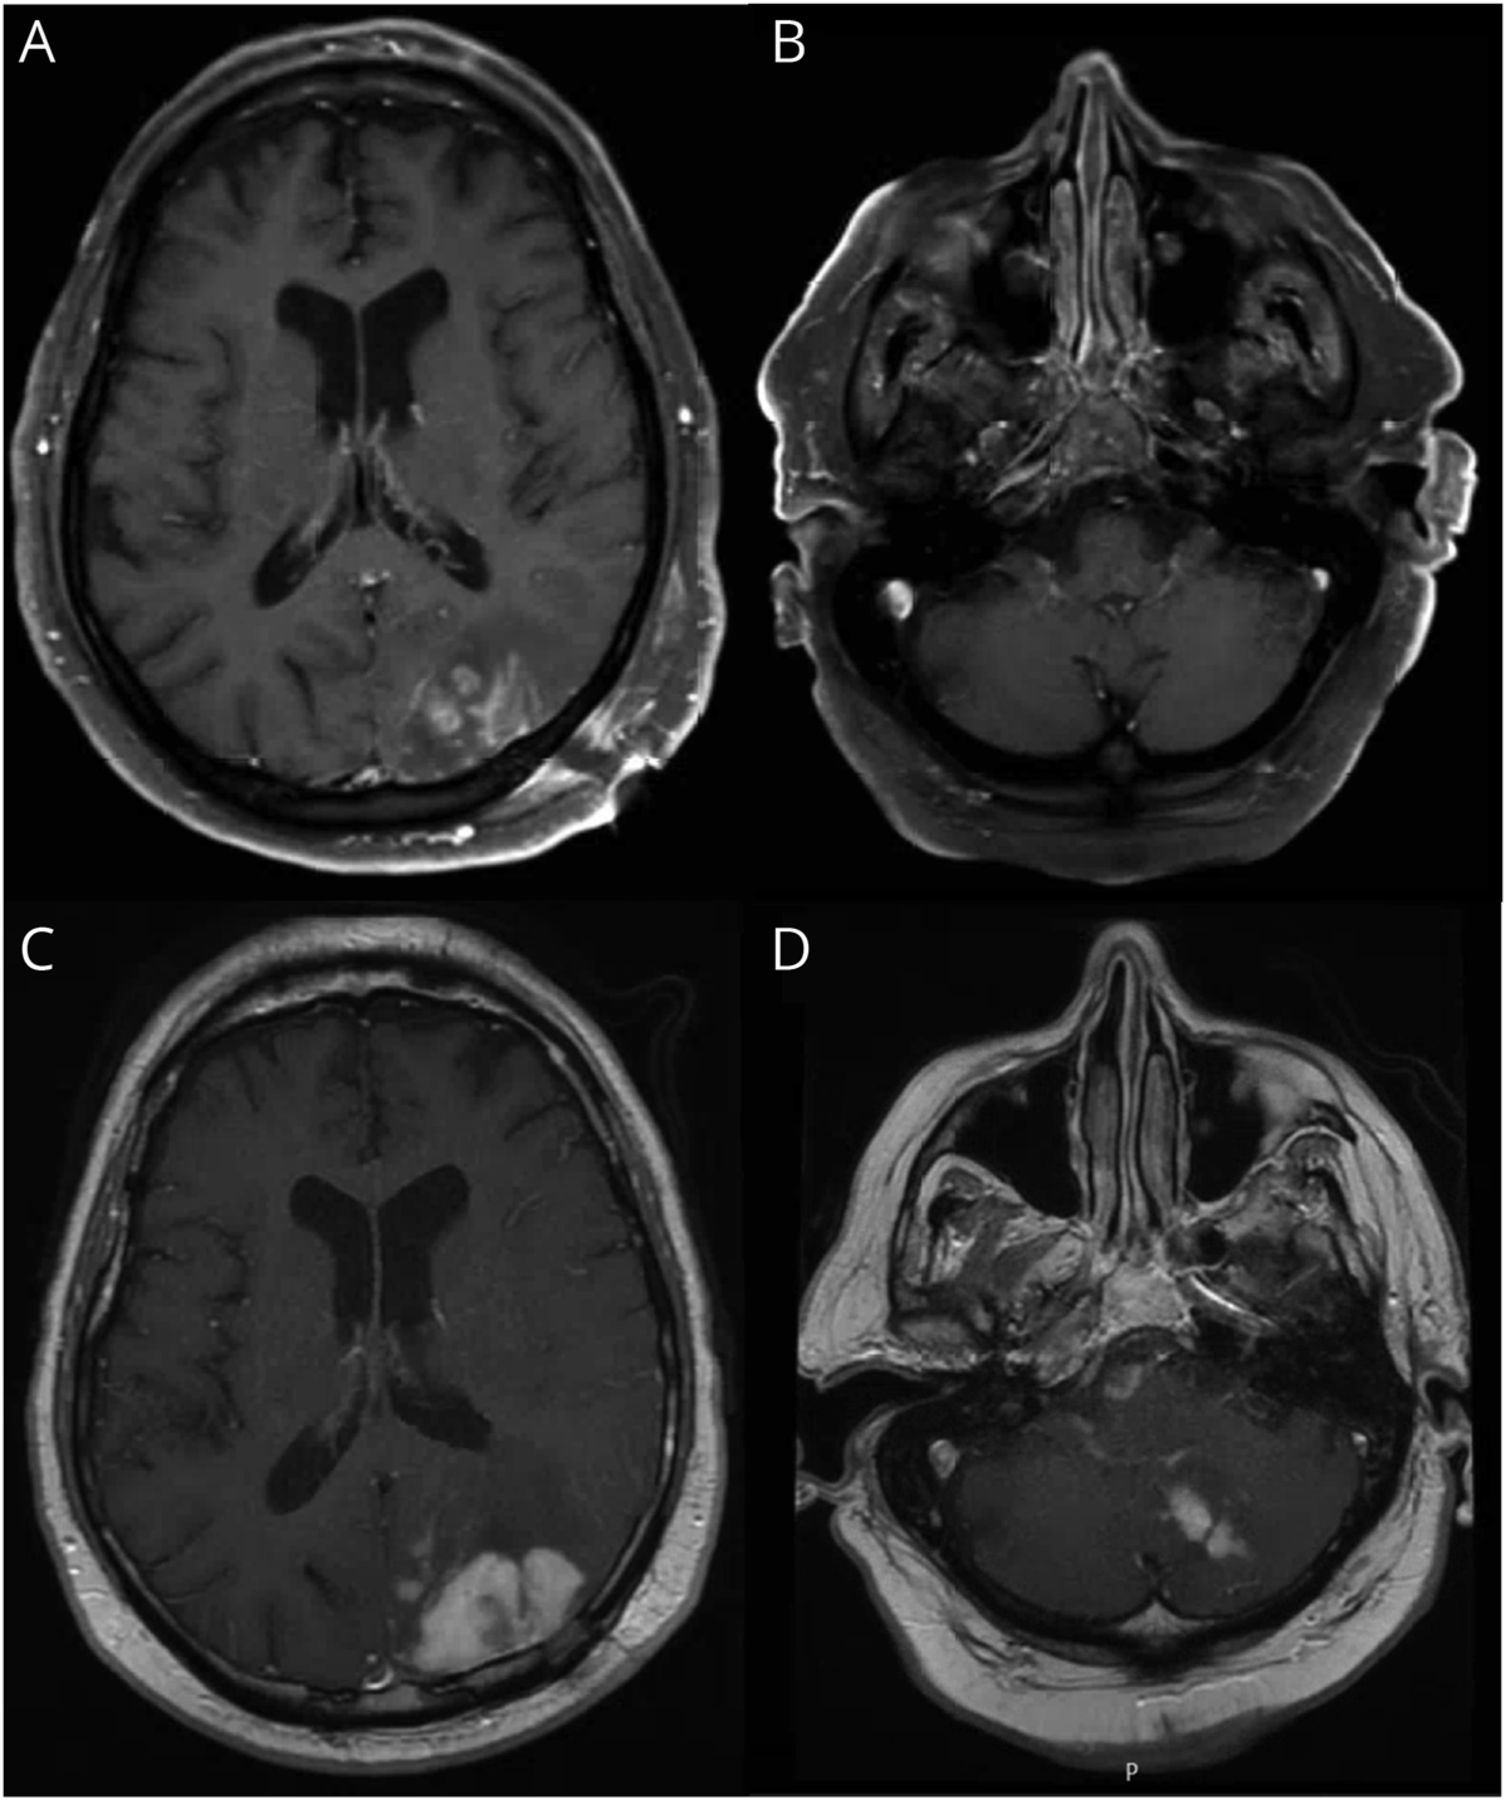

虽然等待结果和活组织检查,病人迅速恶化脑水肿和脑积水和失代偿性的发展。9天内承认,他经历了一个突出的临床事件和死亡。大脑解剖了(图2)。

苏木精和eosin-stained部分演示(A, B)分散的多核巨细胞(黑色箭头)和集群类上皮组织细胞和淋巴细胞(红色箭头)张肿胀、反应性星形胶质细胞(100×放大)。脑膜。地区生产总值(gdp)的出血性坏死披露纤维素样血管炎和microthrombosis,焦血性凝固坏死。200×放大,(C)血管周的聚集的大型细胞被认为在炎性浸润(黑色箭头)。(D)大功率(400×放大)这些细胞的细胞质颗粒,低nuclear-to-cytoplasmic比率,和小而圆核和核仁显著等。这些细胞被确定为Balamuthia mandrillaris营养体。